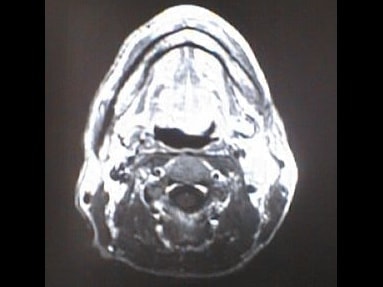

MRI画像比較

入院当時MRI画像①

入院3か月後癌消滅MRI画像①